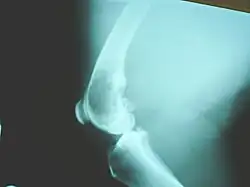

X-ray of osteosarcoma of the distal femur in a dog

Osteosarcoma is the most common bone tumor in dogs and typically affects middle-aged large and giant breed dogs such as Irish Wolfhounds, Greyhounds, German Shepherds, Rottweilers, mountain breeds (Great Pyrenees, St. Bernard, Leonberger, Newfoundland), Doberman Pinschers and Great Danes. It has a 10-fold greater incidence in dogs than humans.[33] A hereditary base has been shown in St. Bernard dogs.[34] Spayed/neutered dogs have twice the risk of intact ones to develop osteosarcoma.[35] Infestation with the parasite Spirocerca lupi can cause osteosarcoma of the esophagus.[36]

The most commonly affected bones are the proximal humerus, the distal radius, the distal femur, and the tibia,[37] following the basic premise "far from the elbow, close to the knee". Other sites include the ribs, the mandible, the spine, and the pelvis. Rarely, osteosarcoma may arise from soft tissues (extraskeletal osteosarcoma). Metastasis of tumors involving the limb bones is very common, usually to the lungs. The tumor causes a great deal of pain, and can even lead to fracture of the affected bone. As with human osteosarcoma, bone biopsy is the definitive method to reach a final diagnosis. Osteosarcoma should be differentiated from other bone tumours and a range of other lesions, such as osteomyelitis. Differential diagnosis of the osteosarcoma of the skull in particular includes, among others, chondrosarcoma and the multilobular tumour of bone.[38][39]